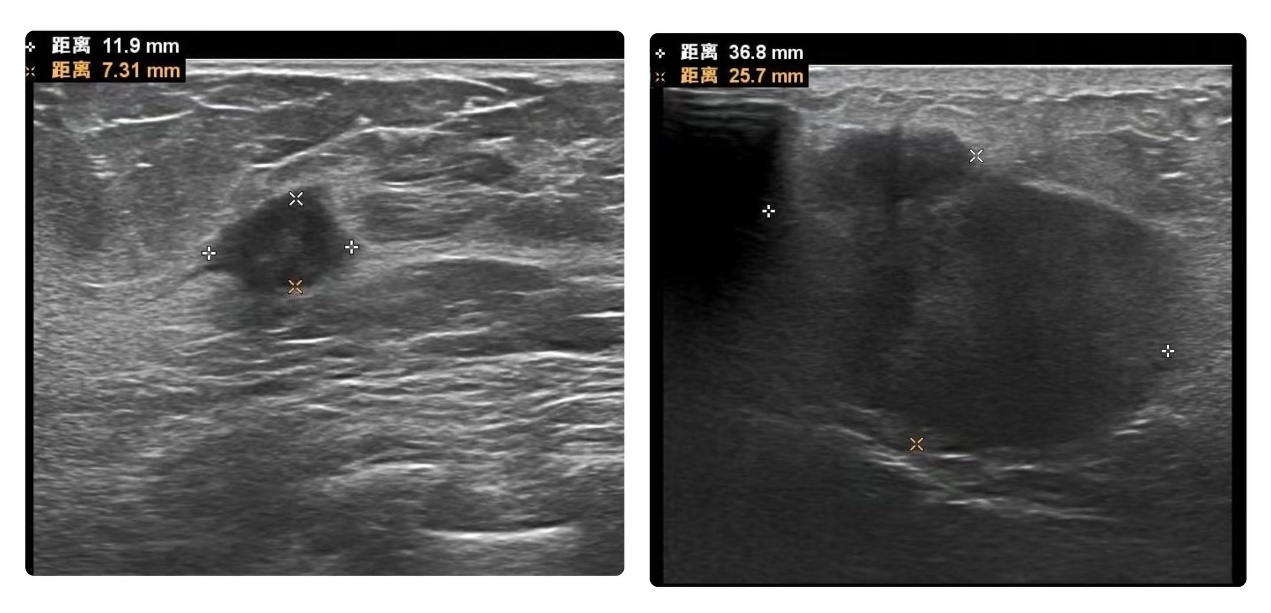

结果提示:左侧乳腺11点及1点方向实性结节,BI-RADS 4C类,右侧乳腺9点方向实性结节,BI-RADS 4a类

乳腺结节4类表示可能存在恶性病变,医生很快给芳姐做了穿刺活检,结果提示:非特殊类型浸润性乳腺癌。